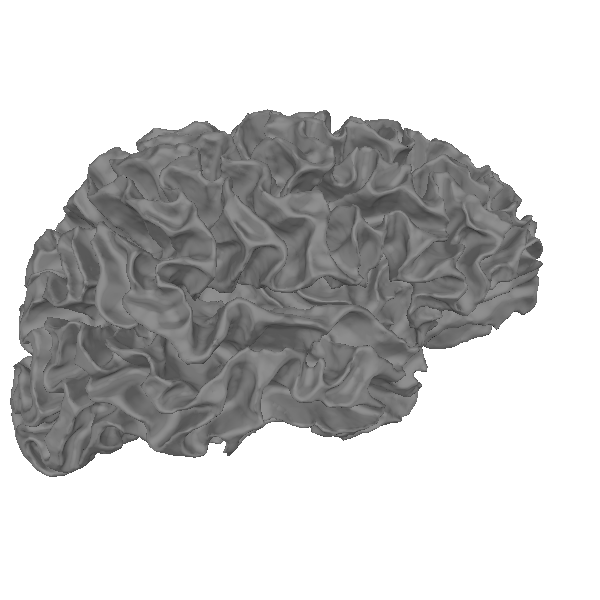

Using FreeSurfer’s surface reconstructions#

An important part of what FreeSurfer does is provide cortical surface

reconstructions. For example, let’s load and view the white surface

of the brain. This is a 3D mesh defined by a set of vertices (conventionally

called rr) with shape (n_vertices, 3) and a set of triangles

(tris) with shape (n_tris, 3) defining which vertices in rr form

each triangular facet of the mesh.

Let’s actually plot it: